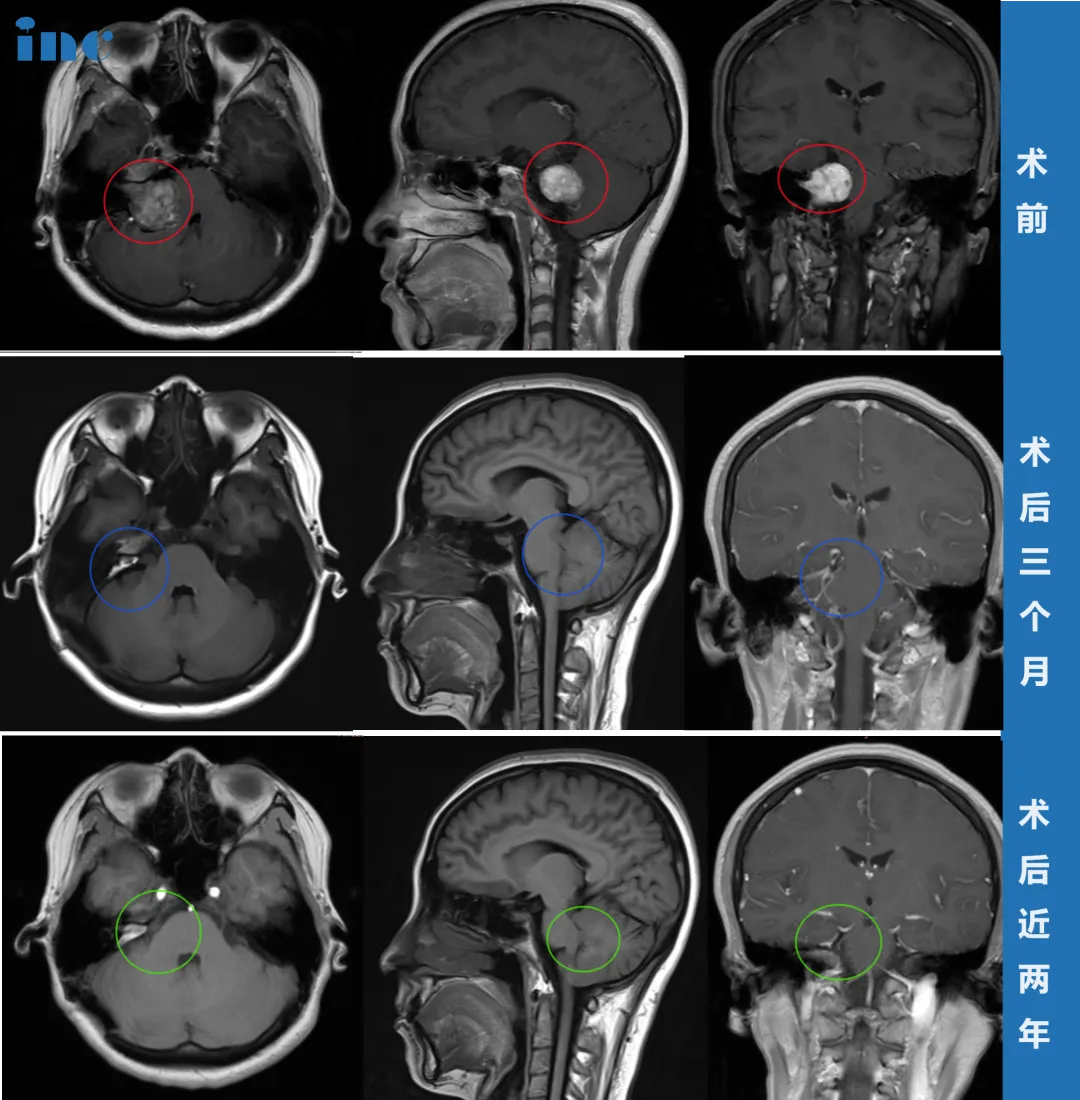

此次,她接受了头颅核磁共振(MRI)检查,结果最终明确了病因——右侧桥小脑角区前庭神经鞘瘤。肿瘤最大直径约35毫米(包括内听道内的部分),已经压迫到脑干,导致桥脑及右侧桥臂受压,第四脑室形态发生改变。

所有准备工作就绪后,巴教授根据肿瘤的具体位置和形态特征,采用适合患者个体情况的手术入路。术中应用神经电生理监测和MRI辅助技术,确保神经功能和重要脑组织不受损伤,在显微镜下完成肿瘤全部切除并经确认。

令人欣慰的是,李女士术后当天即拔除气管插管,可完全自主呼吸。复查CT显示结果正常,未出现脑出血等并发症。

虽然术后因水肿出现了短暂性面瘫,但经过积极康复锻炼,术后两个月基本恢复,半年后恢复状况良好。

术后两年的MRI检查结果更令人满意:肿瘤被完全切除,未见任何复发迹象。目前她的面部功能完全恢复,面部对称,右侧面神经功能良好。